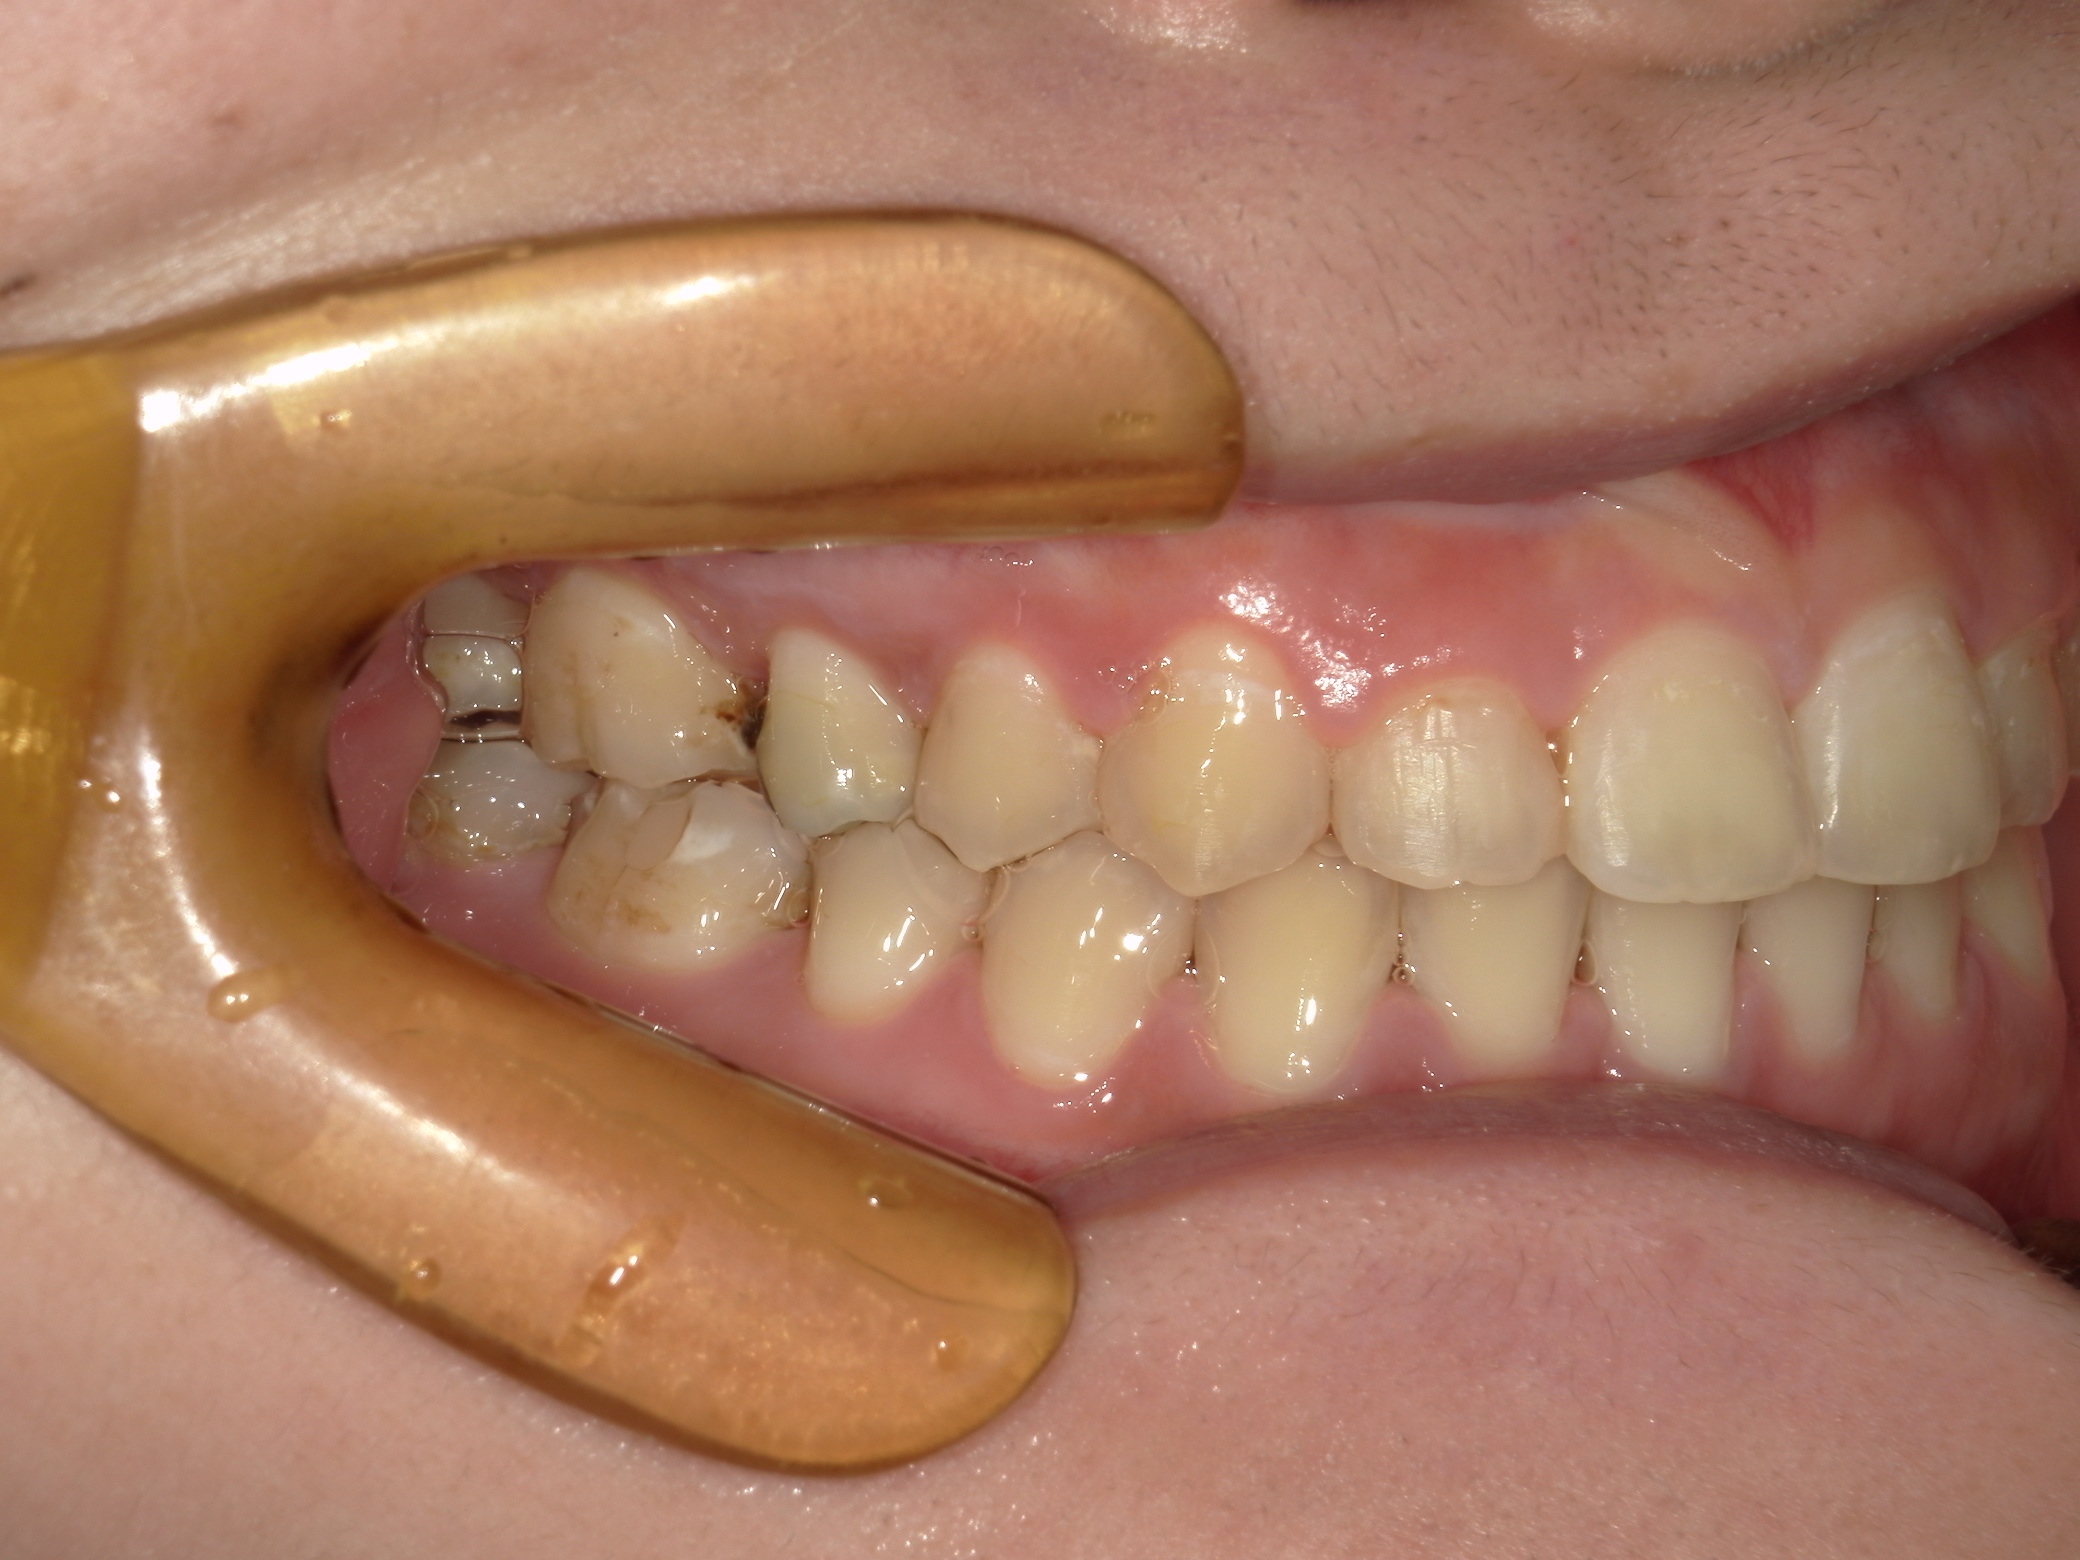

口内左

治療前

治療後